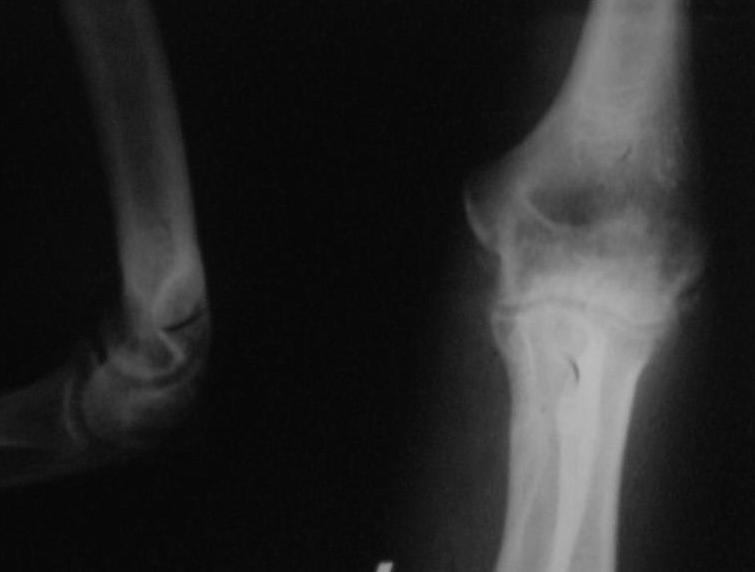

Поступил пациент, 47 лет. травма 15 сентября - вывих предплечья, репозиция. Фиксация 1 месяц. До настоящего времени не обращался. Вот рентенограммы на 2-й и 3-й месяцы после травмы. Неврологии нет. Имеется контрактура локтевого сустава (сгибиние 90, разгибание 120). На снимках что-то похожее на гетеротопические оссификаты, такое впечатление. Как лучше восстановить функцию, возможно ли применить редрессацию? Все-таки локтевой сустав "капризный".С ув. Sergey Melashenko, г. Запорожье

Dear colleguaes! I almost sure this elbow after dislocation and clouse readuction treatment.Despite pure quality of x-ray picture

I suspect small detachment fragment from coronal process.He is lucky guy that haven't instability.

In other side stiff elbow isn't happy prise in the life. In this case I would like to go to open arthrorisis(Column operation ) release anterior joint capsula and after that if you achieve range of movment good on the operation table can use physiotherapy-active assistance exersise and Univerasal elbow brace fixation. If you have not acceptable movement in the operation ( I mean in this case flexion extension 70-150 wiil be good)